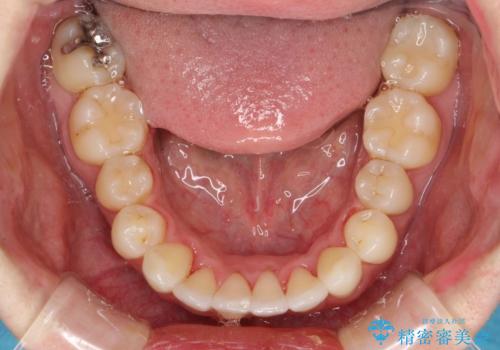

フルリンガル矯正 非抜歯でガタつきを整える

- フルリンガルワイヤーによる非抜歯治療を計画しました。